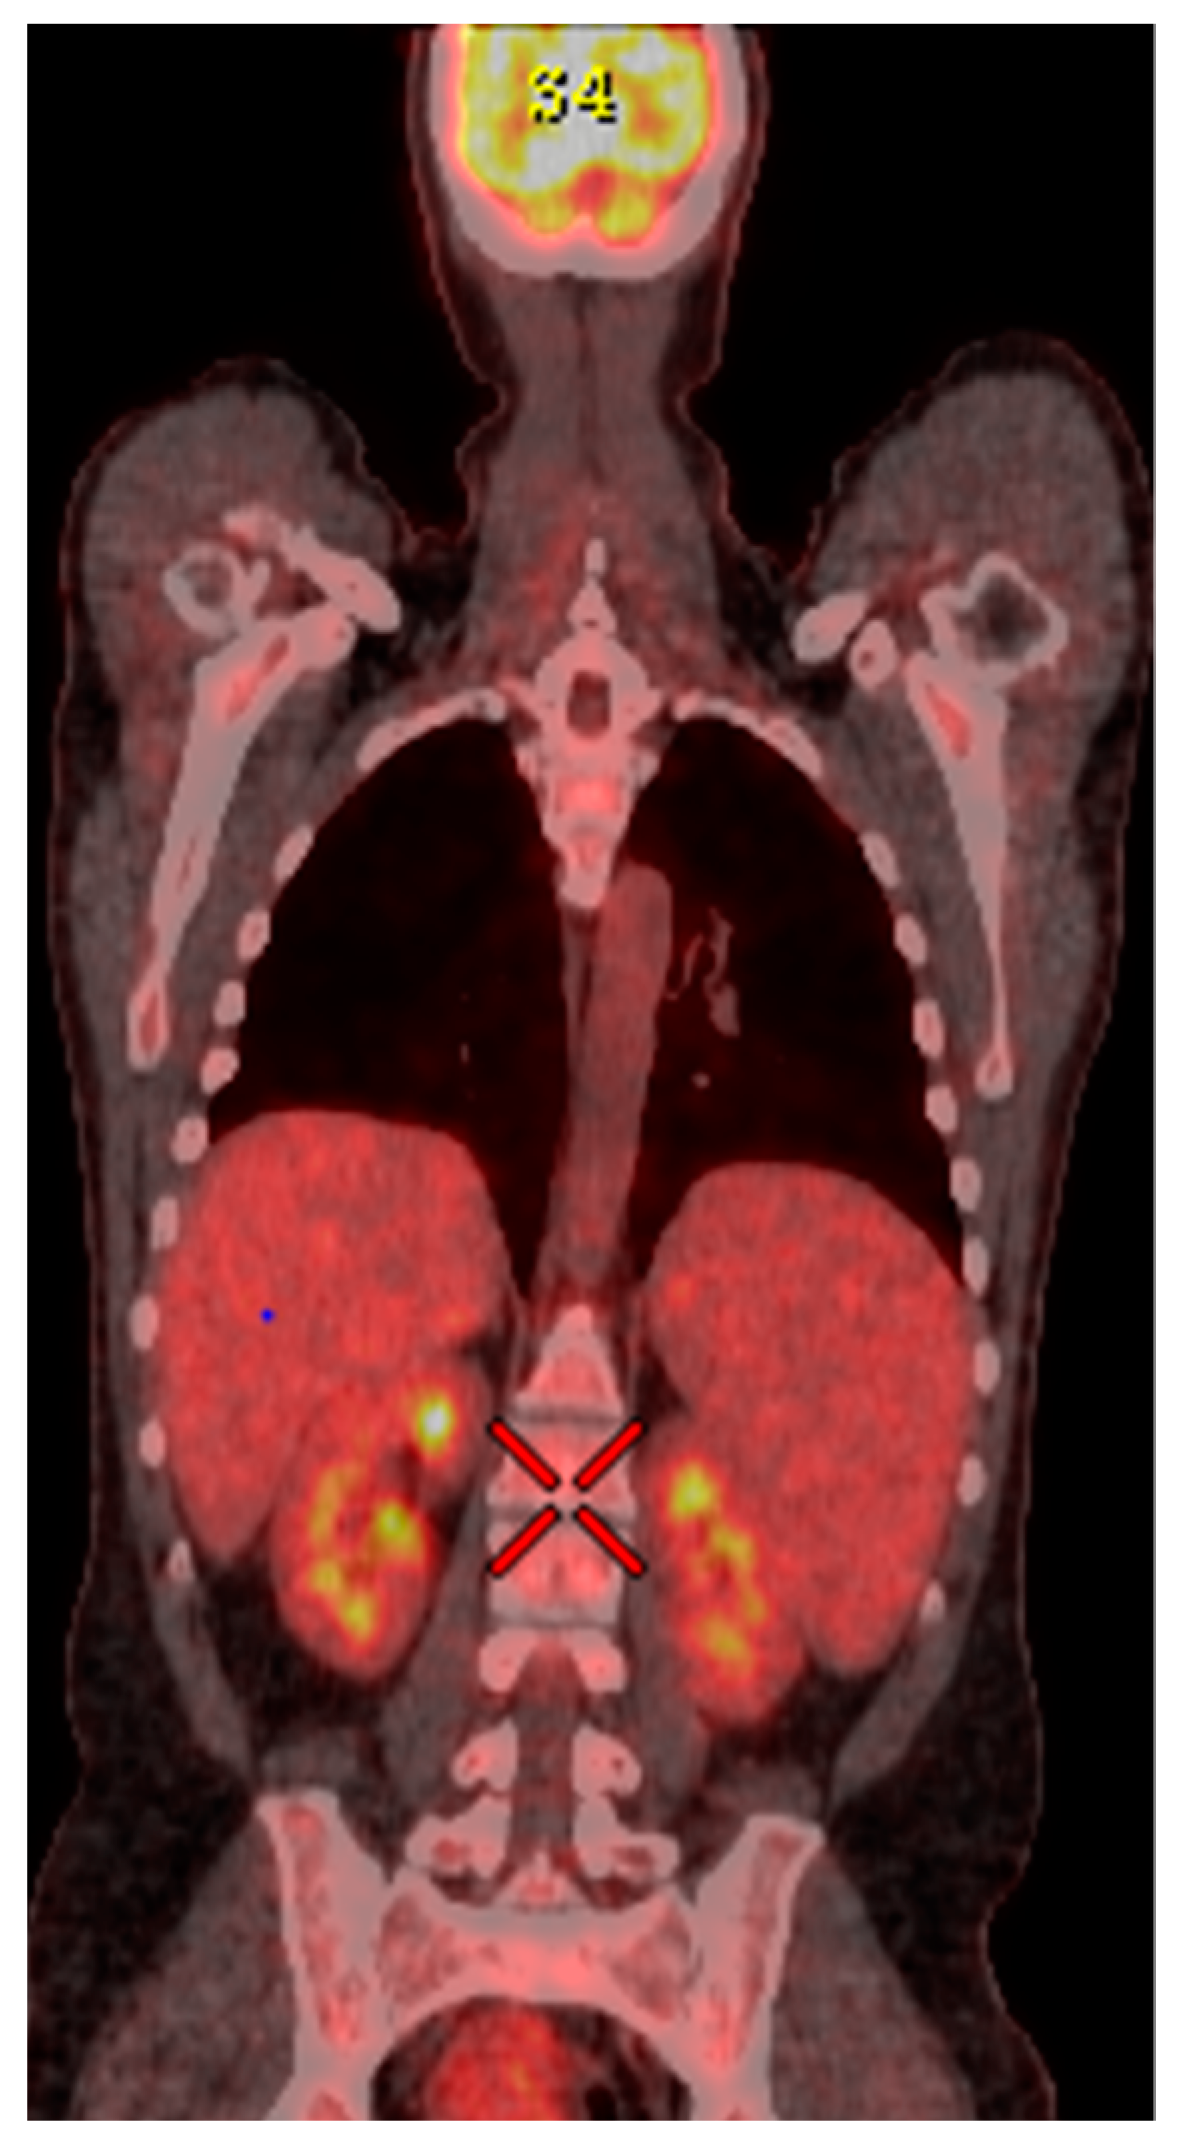

Urine culture revealed positivity for Candida albicans, while three different blood cultures, viral PCR and QuantiFERON TB-Gold test, resulted negative. Conversely, ANA positivity was confirmed (1/80 speckled nuclear pattern), and FDG-PET pointed out an increased glucose uptake in the liver, spleen, and the whole bone marrow (Figure 2).

Figure 2.

18-FDG-PET shows diffuse metabolic activity within the liver, spleen, and whole bone marrow. Characteristics: coronal Ex: 14,321, Se, 12 STATIC, P: 68,36, DFOV: 172.9 × 98.8 cm, M: 13.11 kBq/mL.